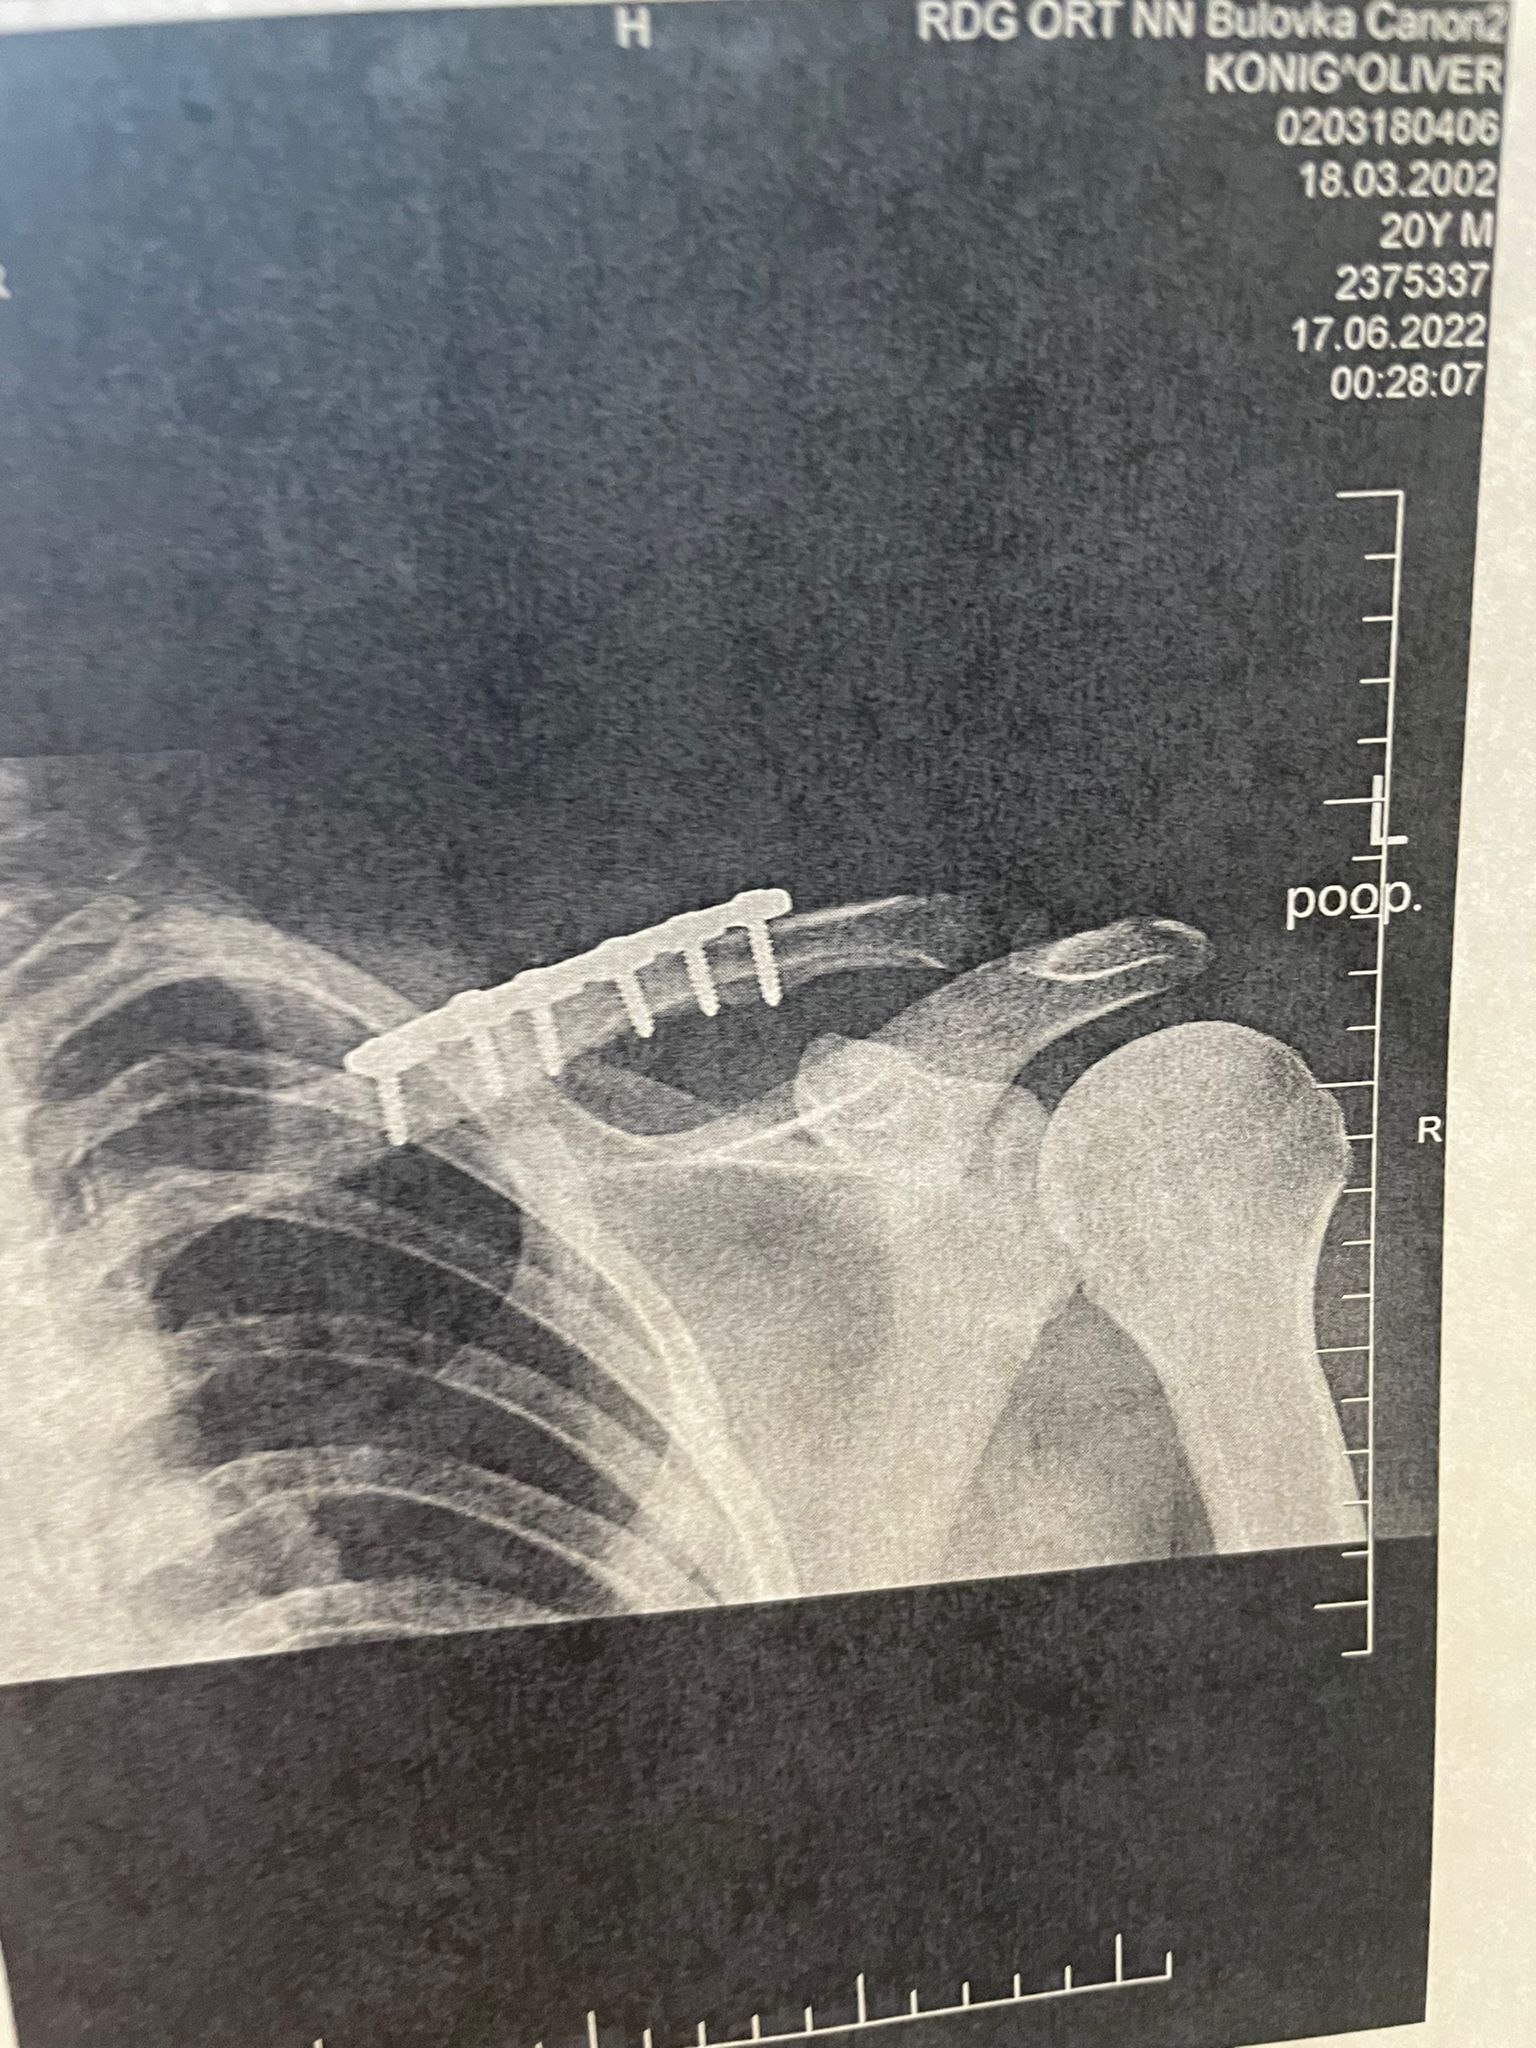

Velká komplikace v jeho první sezoně mezi elitou. Oliver König si během tréninku v Mostě zlomil klíční kost. Nehoda se přihodila před týdnem, český motocyklový jezdec už je po operaci a v ramenou má šest titanových šroubů. To, že se nepostaví na start závodu MS superbiků, si vůbec nepřipouští. „Doktor mi dal do těla nejtužší možné šrouby, prý mi do nich mohou mlátit baseballovou pálkou a nic se mi nestane. Za čtrnáct dní chci být na motorce,“ prohlásil König, kterého závod ve Velké Británii čeká v polovině července a poté už je na programu zastávka v domácím Mostě.

V tu chvíli přišel na Königa ohromný vztek. „Prohodil jsem v duchu všechna sprostá slova, která jsou. Byl jsem na sebe naštvaný,“ doplnil. Jediný český zástupce v mistrovství světa superbiků odjel rovnou do nemocnice Bulovka, kde ho operoval doktor Martin Biegel. „Chci moc poděkovat Ivaně Feiglové, že to zařídila. V týdnu jsem už byl u něj na kontrole a byl překvapený, jak zlomenina a sešití vypadá. V pátek mi vyndají stehy a měl bych začít s rehabilitací. Ta bude probíhat s mým fyzioterapeutem Karlem Holánem. Bude potřeba rameno rozhýbat a nutně ho posilnit,“ tvrdil jezdec z týmu Orelac Racing. „Moc mě to mrzí, protože mě čekali tři dny testů v Mostě a měl jsem další plány.“